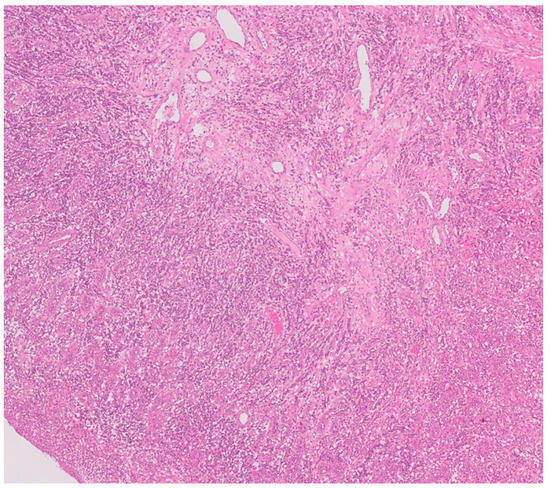

2.4. Surgical Management

2.5. Results